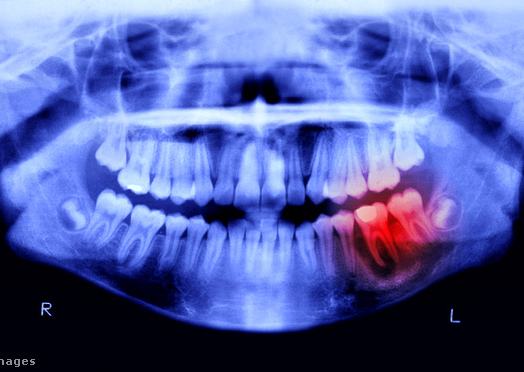

Az Európai Unióban teljes körű tilalmat vezettek be a fogászati amalgám használatára. Ez annak az intézkedéscsomagnak a része, amelynek értelmében uniós tilalom alá esik minden higanyt tartalmazó termék gyártása, behozatala és kivitele.

Az Európai Unió Tanácsa által elfogadott rendelet értelmében 2025. január 1-jétől mindenki számára tilos lesz a fogászati amalgám használata. Eddig a szabályozás csak a 15 év alatti gyermekekre, állapotos és szoptató nőkre vonatkozott, de az új rendelkezések kiterjesztik a tilalmat mindenki másra is – adták hírül a testület honlapján.

A fogászati amalgám kivitele 2025. január 1-jétől válik tilossá, míg az EU-ban történő gyártás és behozatal 2026. július 1-jével szűnik meg. A fogorvosoknak mindazonáltal lehetőségük lesz kivételt tenni, amennyiben úgy ítélik meg, hogy páciensük esetében a fogászati amalgám használata elengedhetetlen. Persze, hogy az ehhez való anyagot honnan szerzik majd be, ha gyártási és behozatali tilalom alá esik, az még a jövő zenéje. Annyit lehet most tudni, hogy az Európai Unió Bizottsága 2029. december 31-ig felülvizsgálja majd a fogászati amalgám használatára vonatkozó kivételeket, figyelembe véve a higanymentes alternatívák elérhetőségét.